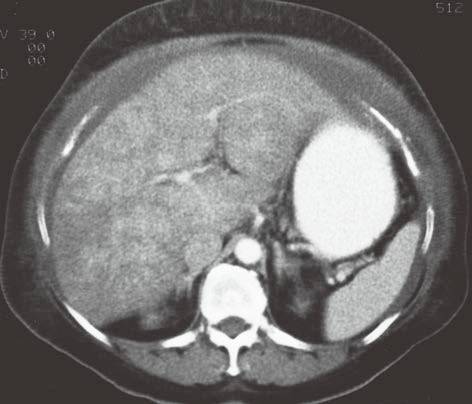

| 布加综合征(图4 和图 5) | 肝脏体积增大,密度弥漫性减低(由肝实质充血造成)。 | 在肝内静脉、肝静脉或下腔静脉肝上段流出道梗阻。少见,与髙凝状态、口服避孕药、怀孕、浸润性肿瘤和先天性瓣膜有关,“翻转”式对比增强(见图5)。 |

图4布加综合征

图5布加综合征